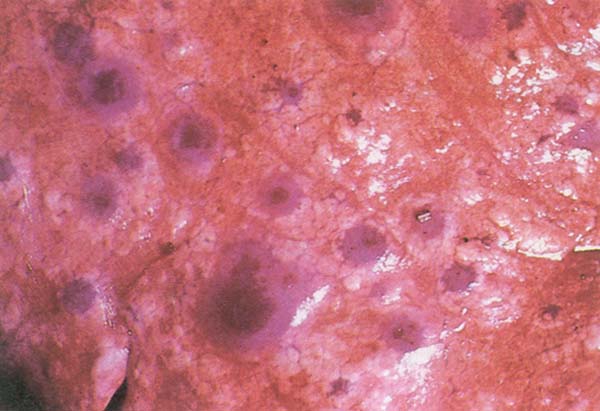

- Kuzularda karaciğer nekrozu (karaciğer benekli gri veya kırmızımsı kahverengiden parlak sarıya kadar değişebilir)

- Fetusta ve hemotoraksta kanamalar (Şekil 150)

Karar : Rift Vadisi ateşinin klinik belirtilerini gösteren bir hayvanın karkası kınanır . Reaktörler ve kurtarılan hayvanlar onaylanır . Karkasın etkilenen kısımları, karaciğer ve kan kınanmalıdır.

Şekil 150 : RVF. Fetusta hemorajiler ve hemotoraks.